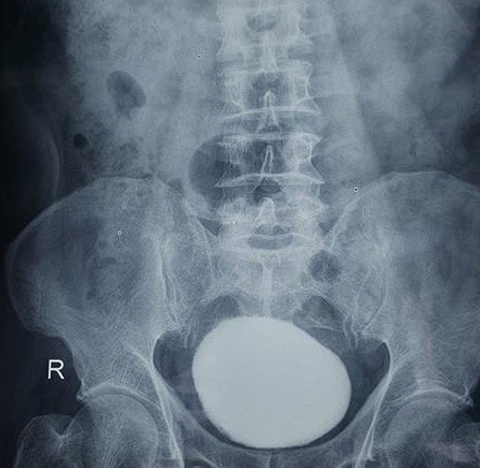

Sau thăm khám, các bác sĩ phát hiện một khối cứng trên xương mu. Làm thêm siêu âm X-quang ổ bụng, cho thấy bệnh nhân bị sỏi bàng quang kích thước lớn, chiếm gần hết thể tích bàng quang, chèn ép gây giãn niệu quản và đài bể thận phải.

| Viên sỏi chiếm gần hết thể tích bàng quang |